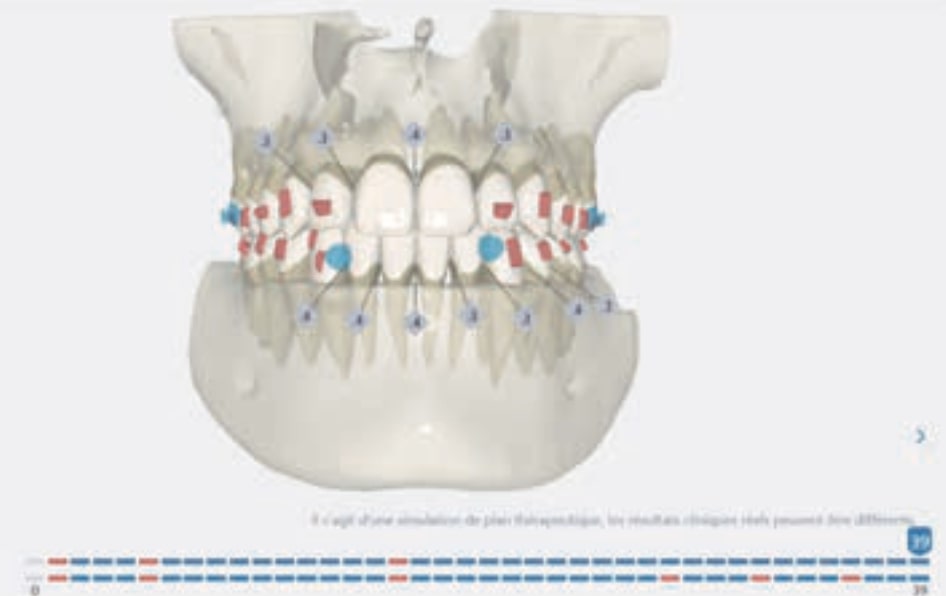

- Distalization of the Third and Fourth Quadrants: Move the teeth distally in these quadrants to achieve a Class I relationship using the A8 protocol, improving the patient’s dental alignment and occlusion.

- Solve the Crossbite of Tooth 33: Correct the position of tooth 33 to eliminate the crossbite, contributing to a more balanced occlusion.

- Intrusion of the Lower Anterior Teeth: Adjust the vertical position of the lower anterior teeth to level the curve of Spee, improving the harmony of the occlusion.

- Improve the Root Position of Teeth 33 and 43: Optimize the position of the roots of teeth 33 and 43 in relation to the cortical bone to ensure adequate bone support and long-term stability.

Treatment setup